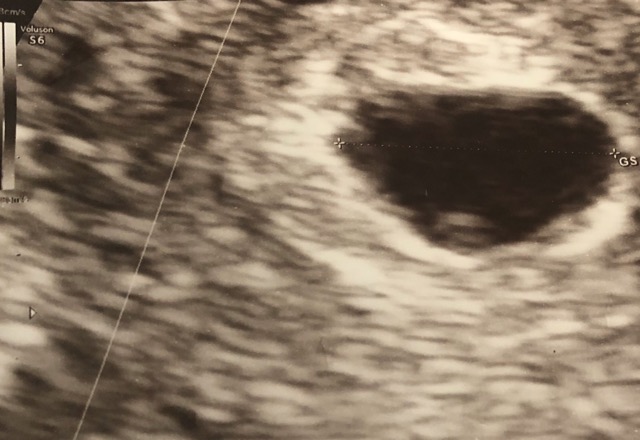

I am 6 weeks pregnant and i went to my oby today and he said cant detect the baby heart beat yet he told me the baby still 5 weeks 2 days and i got a light pink blood this morning while i wipe a toilet paper after hr ago its gone but he gave me a duphaston so my next appoinment is feb 13,2020 hope that time i can hear my prince or princess heart beat